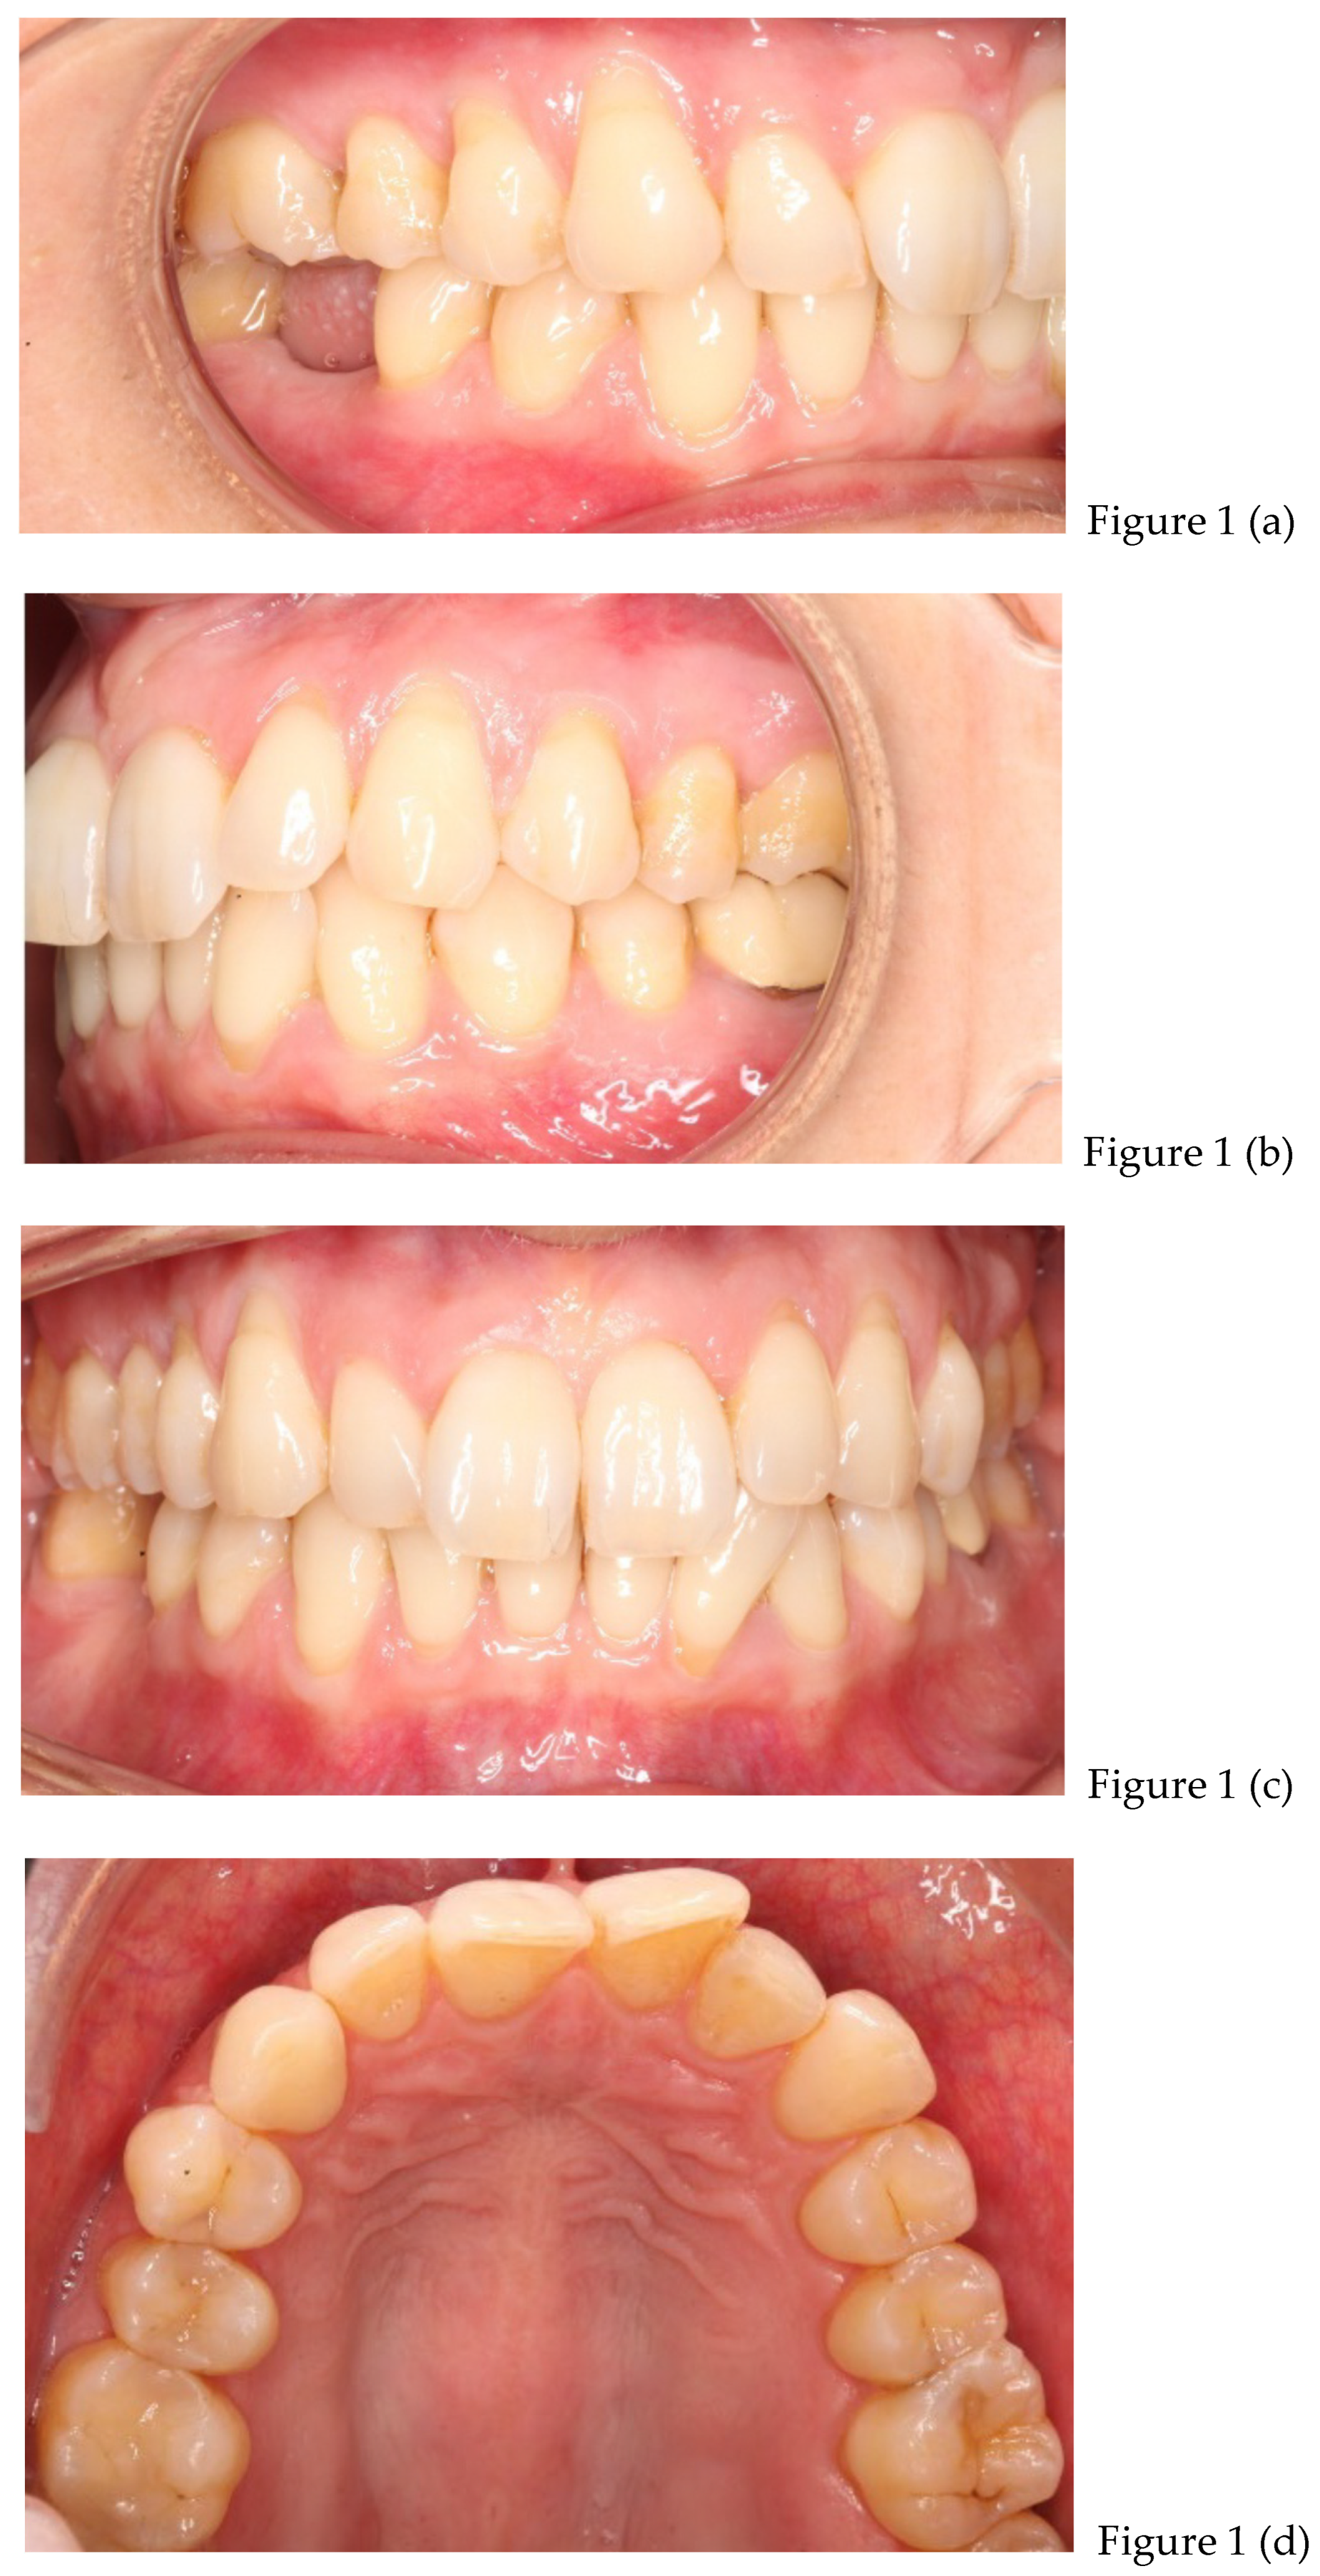

| preliminary photos | |

| after 8 months | Retainers + CBCT (t1) + final photos |